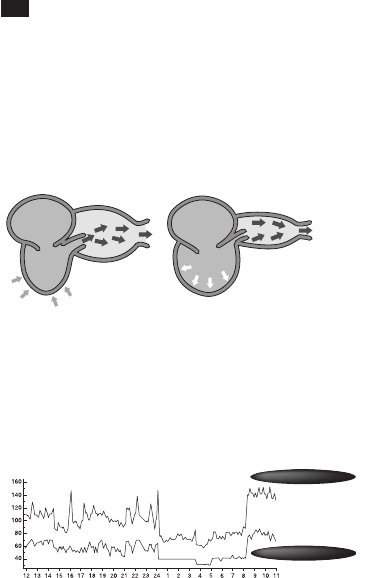

Der Blutdruck ist jener Druck, den Herz- und Gefäßsystem aufbauen,

damit eine geringe Blutmenge den gesamten Organismus rasch

und ununterbrochen durchströmen kann. Der Blutdruck verläuft als

Wellenbewegung. Der Wellengipfel entspricht dem systolischen (oberen)

Wert, wenn das Blut in die Adern gepumpt wird. Das Wellental entspricht

dem diastolischen (unteren) Druck, wenn das Blut zum Herzen

zurückfließt.

(Systolisch)

(Diastolisch)

Arterie Arterie

Linker

Herzvorhof

Linke

Herzkammer

Linker

Herzvorhof

Linke

Herzkammer

Ausdehnung

Die Arterienwand dehnt

sich aus.

Kontraktion

Der Normalzustand der

Arterienwand wird wieder hergestellt.

Der Blutdruck ändert sich ständig

Der Blutdruck ist kein fix regulierter Wert und je nach Alter, Geschlecht

und einer Reihe weiterer Faktoren unterschiedlich. Er wird wird

tagsüber wahrscheinlich durch Ihren Biorhythmus sowie auch durch die

Körperhaltung, körperliche und geistige Aktivitäten, Ihr Stressniveau

und sogar die Lufttemperatur beeinflusst. Beim Gesunden schwankt der

Blutdruck im Tagesverlauf im Allgemeinen.

Blutdruckwert (mmHg)

Tageszeit

Systolischer Blutdruck

Diastolischer Blutdruck